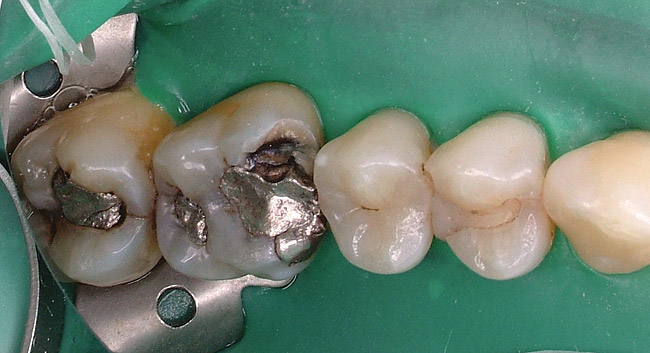

Replacement of existing restorations is responsible for 75% of all operative dentistry.15,19 The reasons for placement and replacement of restorations of direct restorative materials include: primary caries (Figure 1 and Figure 2); recurrent caries (Figure 3); poor margins (Figure 4 and Figure 5); restoration fracture (Figure 6 and Figure 7); tooth fracture (Figure 8); esthetics (Figure 9); non-carious tooth structure lost (attrition, abrasion, abfraction, erosion) (Figure 10); and pain/sensitivity.

Figure 6  Restoration fracture. Fractured isthmus of an amalgam restoration.

Figure 6